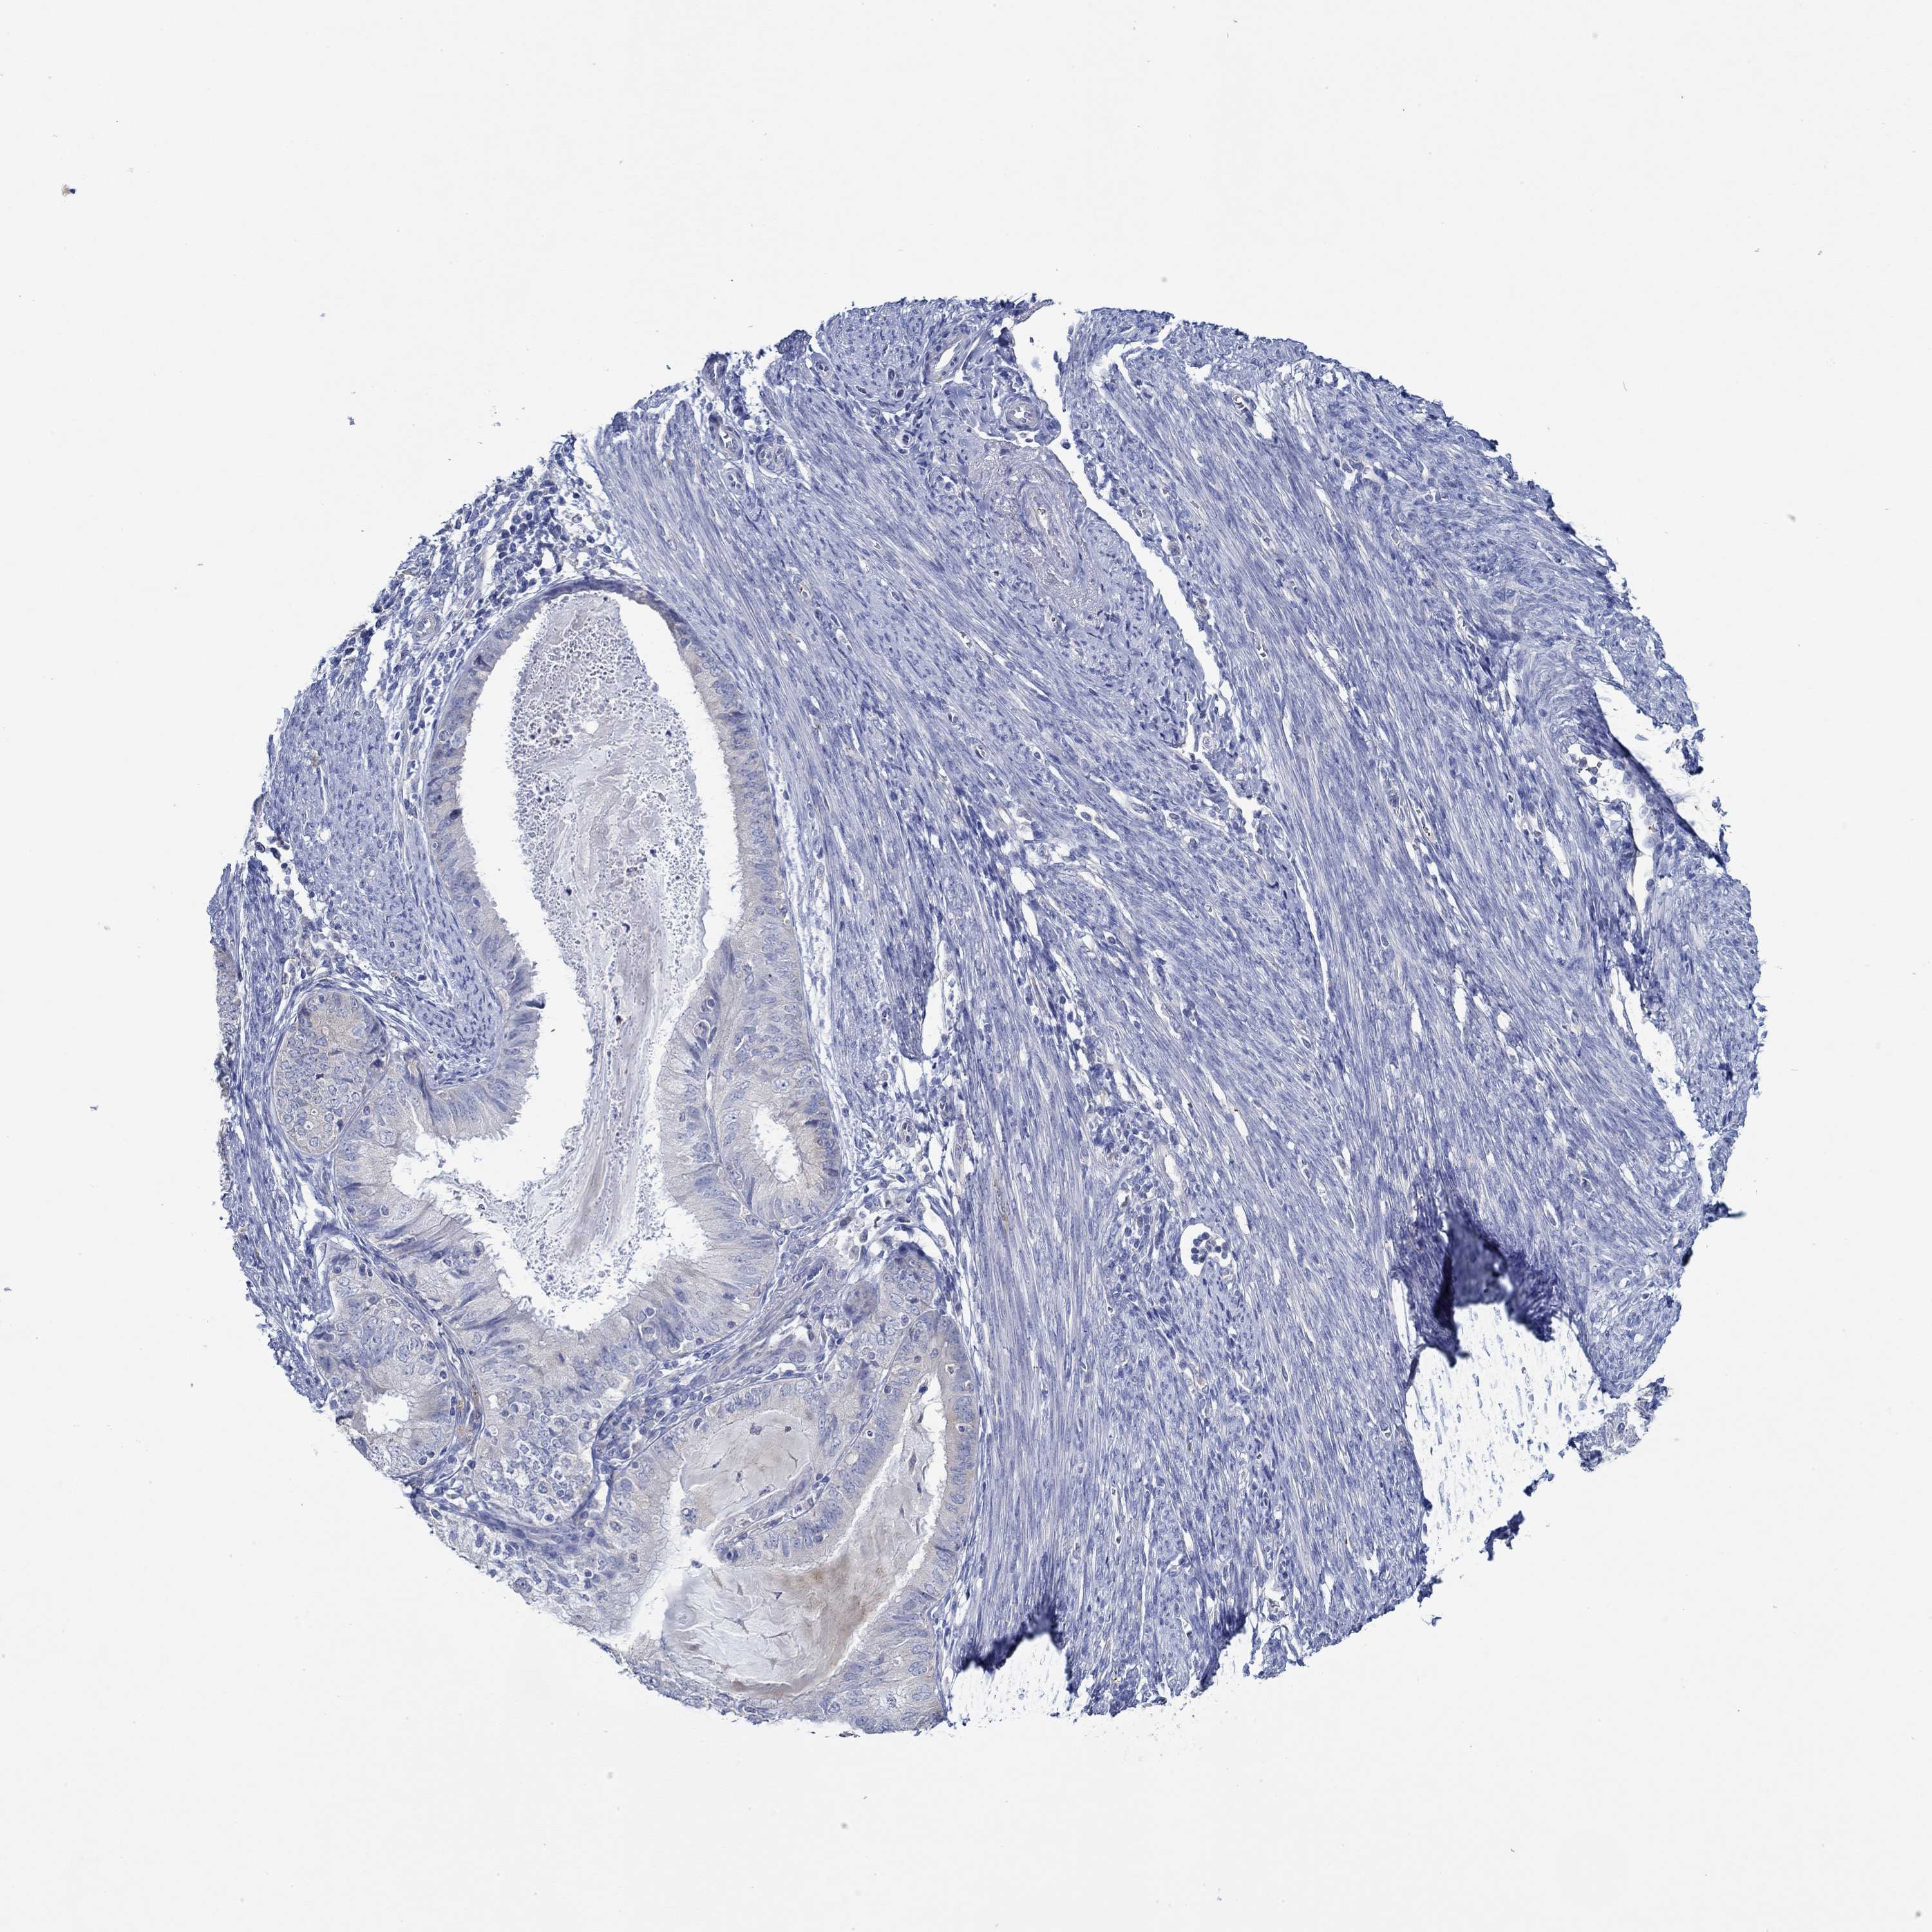

ENDOMETRIAL CANCER - Protein expressioni

A mouse-over function shows sample information and annotation data. Click on an image to view it in a full screen mode. Samples can be filtered based on level of antibody staining by selecting one or several of the following categories: high, medium, low and not detected. The assay and annotation is described here.

Note that samples used for immunohistochemistry by the Human Protein Atlas do not correspond to samples in the TCGA dataset.

Antibody stainingi

Antibody staining in the annotated cell types in the current human tissue is reported as not detected, low, medium, or high, based on conventional immunohistochemistry profiling in selected tissues. This score is based on the combination of the staining intensity and fraction of stained cells.

Each image is clickable and will lead to virtual microscopy that enables deeper exploration of all samples and also displays staining intensity scores, fraction scores and subcellular localization as well as patient and tissue information for each sample.

Antibody HPA067508

Antibody CAB080514

Antibody CAB080517

Staining

High

Medium

Low

Not detected

Intensity

Strong

Moderate

Weak

Negative

Quantity

>75%

75%-25%

<25%

None

Location

Nuclear

Cytoplasmic/membranous

Cytoplasmic/membranous,nuclear

Adenocarcinoma, NOS

Adenocarcinoma, metastatic, NOS